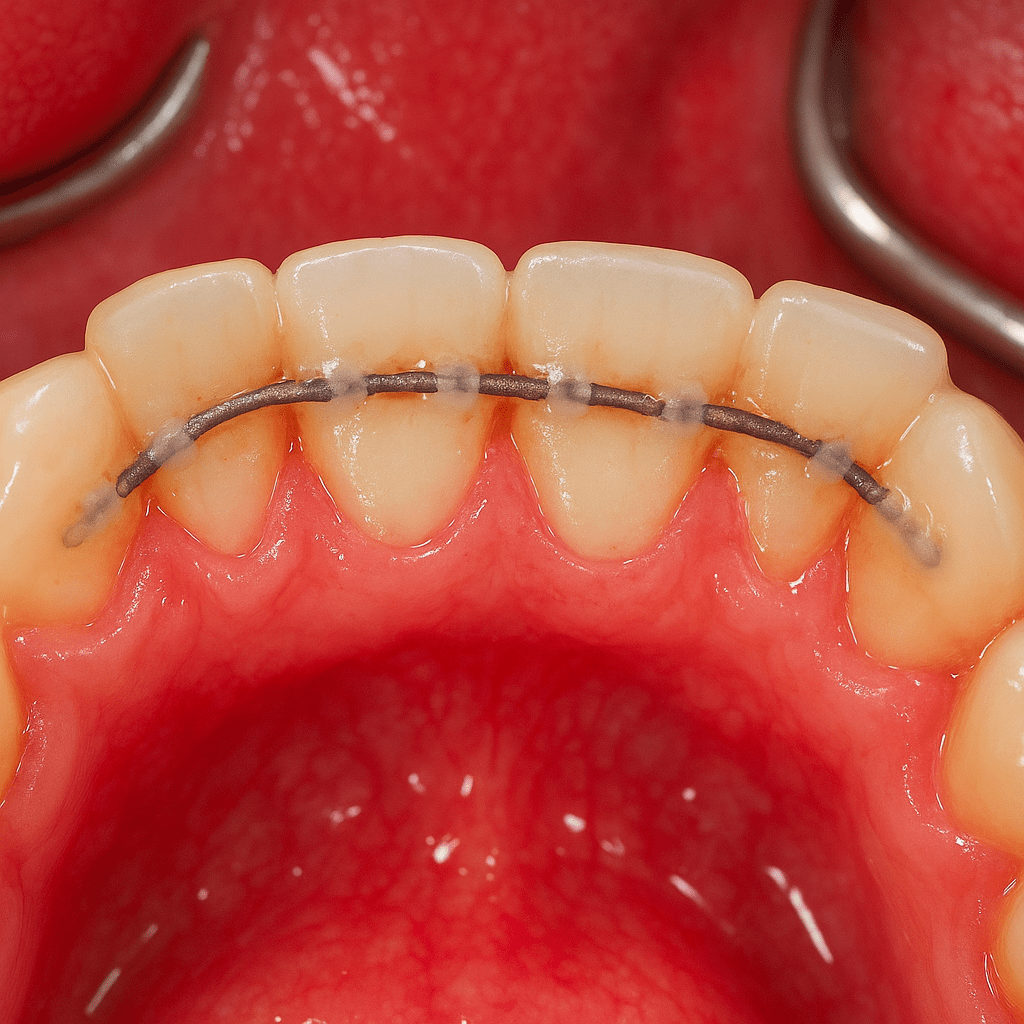

Szynowanie polega na trwałym połączeniu rozchwianych zębów za pomocą cienkich pasków z włókna szklanego lub materiałów kompozytowych. Dzięki temu możliwe jest ich ustabilizowanie, zmniejszenie ruchomości i poprawa komfortu gryzienia. Często jest to jedyny sposób na uniknięcie usunięcia zęba. Dodatkowo, leczenie może obejmować higienizację jamy ustnej, kontrolę stanu przyzębia, a także zalecenia dotyczące codziennej pielęgnacji – wszystko po to, by nie tylko zatrzymać problem, ale też zapobiec jego nawrotom.

Jedną z najczęściej stosowanych metod jest tzw. szynowanie, czyli stabilizacja rozchwianych zębów za pomocą cienkiej taśmy z włókna szklanego lub materiału kompozytowego. Szyna zakładana jest zazwyczaj po wewnętrznej stronie zębów, co sprawia, że jest niemal niewidoczna. Cały zabieg jest bezbolesny i trwa kilkanaście minut, a jego efektem jest zauważalna poprawa komfortu pacjenta – zęby przestają się ruszać, a ryzyko ich utraty znacząco się zmniejsza.

Na czym polega szynowanie zębów?

To metoda mechanicznego ustabilizowania zębów poprzez ich połączenie specjalnym materiałem, najczęściej włóknem szklanym lub kompozytem. Szyna montowana jest od wewnętrznej strony zębów, więc jest praktycznie niewidoczna.